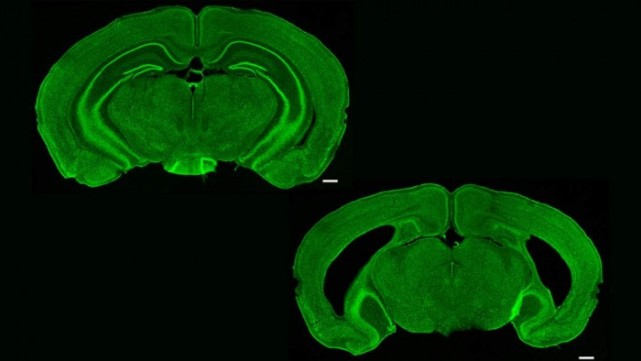

小鼠脑冠状切面

小鼠鼠脑冠状面神经元精细双色图